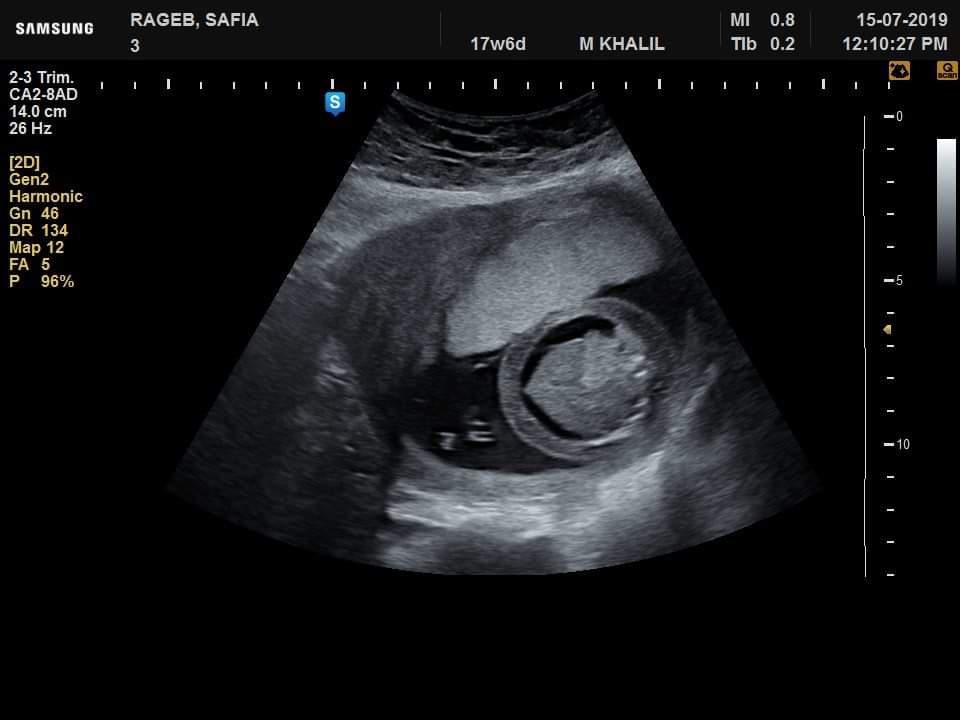

نجح فريق طبى من قسم النساء والتوليد فى مستشفى جامعة كفر الشيخ، فى تشخيص عدد من الحالات، منها حالة تم تحويلها إلى مستشفى الجامعة بسبب وجود زيادة فى السائل الأمنيوسى، وبعد توقيع الكشف وتصوير للجنين تفصيليا تم اكتشاف وتشخيص جنين داخل رحم أمه وبهesophageal atresia (EA) and a tracheoesophageal fistula إنسداد المرئ ووجود ناصور بين القصبة الهوائية والمرئ Agenesis of the corpus callosum عدم تكوين الجسم الثفنى الذى يصل فصى المخ سويا وجود Clubfoot (talipes equinovarus) تشوه فى القدم وابتعاد الأصبع الكبير للقدم عن الإصبع الآخر وزيادة فى السائل الأمنيوسى تم بذل لتر و800 سم من السائل الأمنيوسى وإرسال بعضه للتحليل الكروموسومي.

وأوضح الفريق الطبى فى قسم النساء والتوليد بمستشفى جامعة كفرالشيخ، أنه تم تشخيص حالة أخرى استسقاء لجنين داخل الرحم لأسباب جينية، وحالة أخرى بضمور كليتى الجنين وهذا التشخيص المبكر يساعد على مساعدة الجنين الأول بعمل عملية له بعد الولادة لإصلاح الإنسداد بالمرئ وإصلاح الناصور أما فى الحالتين الثانيتين فينصح بعدم تعرض الأم لعمل عملية قيصرية فى مثل هذه الحالات.